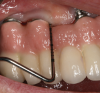

Personal hygiene aids: manual and electric toothbrushes, dental floss, interproximal brushes, and antimicrobials. For single implants or fixed multiunit implant-supported prostheses, plaque deposits may be managed using a manual or powered toothbrush with floss or an interdental brush.67 Interproximally, interdental brushes with plastic coated wire reduce scratching of implant surfaces (Figure 2).80 Floss threaders are an important aid for use with multiunit prostheses.72 Subgingival irrigation with or without antimicrobials (eg, chlorhexidine) can also be used as an adjunct to reduce plaque deposits.75,76,81 Patients should be instructed to brush implants twice daily to reduce bacterial plaque accumulations.64

Fig 2. Interproximal brushes available in various shapes and diameters can be used for interproximal plaque control.

Figure 2